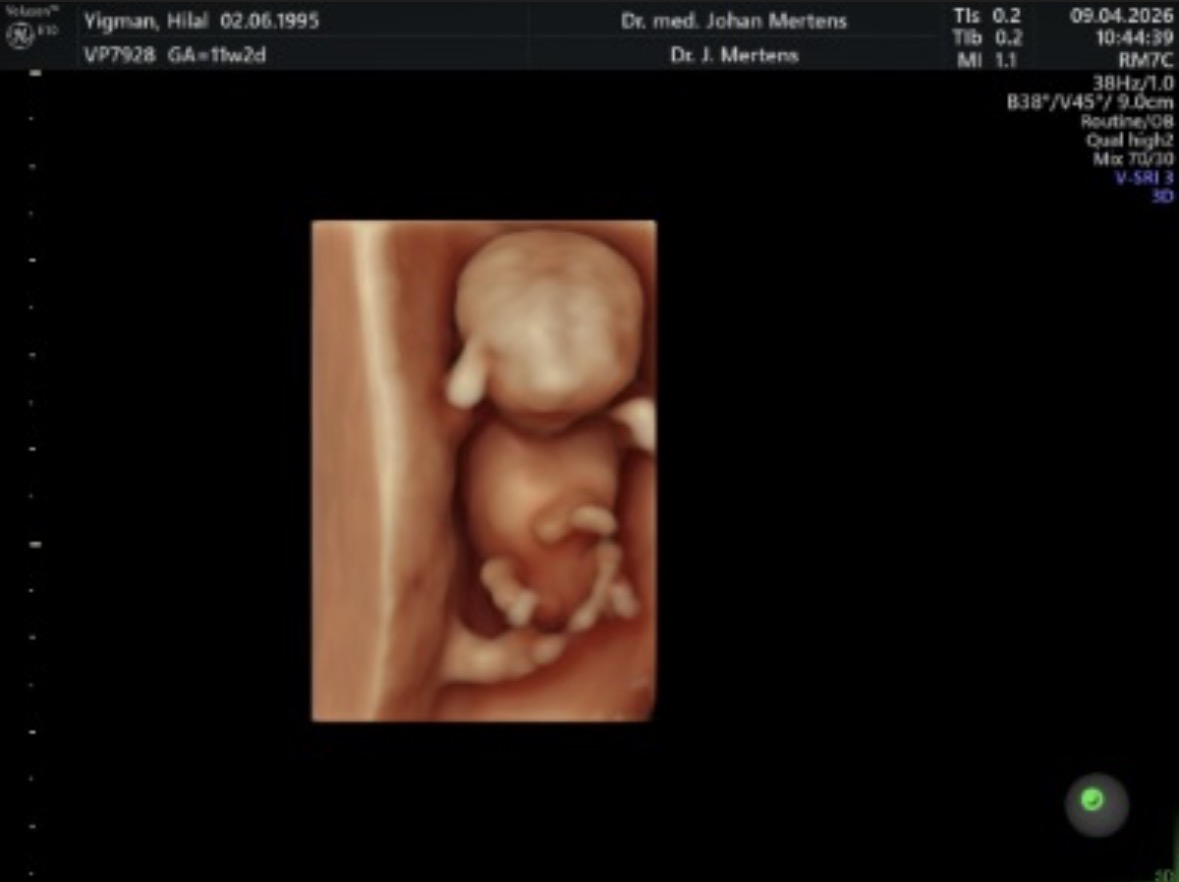

Bana da 16.haftada ve 17 de net soyledıler.Dün detaylıda da aynısı soylendi umarım değişmez

Erkek bebekler daha mı erken gosteriyor benim doktorum 11.haftada tahmin etmişti 14 de net soylemisti @Leyla1991

Bilemiyorum ama bebekten bebeğe değişiyor olabilir bende 11 haftalıkken ikili teste öğrendim cinsiyetini 3 gebeligimi ve hatta yanlışdir diye kontrol zamanı kendi Dr sormuştum oda doğru demişti